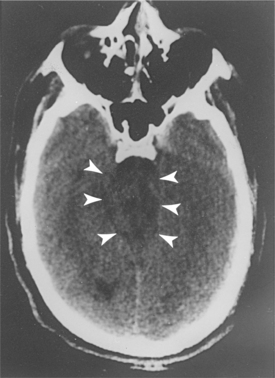

Diagnostic imaging can provide significant information, which can guide the intervention and allow a more accurate prognosis. CT is the primary imaging modality for the initial diagnosis and management of the head-injured person. CT scanning of the head reveals the presence of hemorrhage, swelling, or infarction. In individuals with traumatic coma, patterns on CT that have been associated with worse neurologic outcome include lesions in the brainstem, encroachment of the basal cisterns, and diffuse axonal injury (Fig. 33-7).51 An initially normal CT scan, however, is no assurance that hemorrhagic lesions will not occur.

Figure 33-7 CT scan of the head in a patient with a closed head injury. Severe compression of mesencephalic cisterns is seen, indicating midbrain compression. (Reprinted from Townsend CM: Sabiston textbook of surgery, ed 17, Philadelphia, 2004, Saunders.)

Diffuse axonal injury (DAI) is a frequent CT and pathologic correlate of severe TBI, accounting for about 50% of primary brain injuries. DAI is usually associated with a poor outcome. DAI is readily identifiable on CT as multiple punctate hemorrhages, typically in the deep white matter and corpus callosum and occasionally in the brainstem. DAI may also occur as a result of mild TBI and may culminate in subtle types of cognitive deficits. Approximately 10% to 15% of individuals with clinically severe TBI have a normal CT scan. In such situations, the possibility of extracranial or intracranial vascular disruptions may exist, and angiography should be considered.18